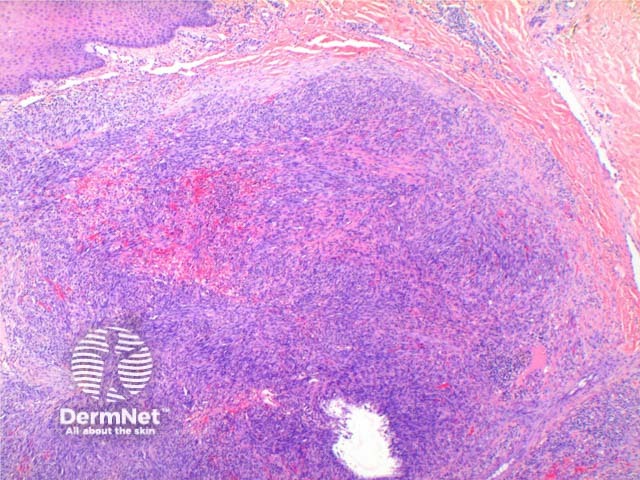

The low power view of the histology of Kaposi sarcoma is of a cellular dermal nodule (Figure 1). There may be varying degrees of overlying epidermal changes which can range from prominent hyperkeratosis and acanthosis to frank ulceration. The dermal proliferation is comprised of a spindle cell proliferation of endothelial cells forming sinuous vascular spaces. These may be sparse in patch phase lesions, progressing to fascicles of spindle cells in nodular lesions (Figures 2,3). This fascicular pattern has been likened to schools of fish. The spindle cells infiltrate through the collagen, forming slit-like spaces, especially towards the periphery of the lesions (Figure 4). Where the newly formed vessels project into an existing space the promontory sign is seen (Figure 5). This is now recognised as not being specific to this condition.

Figure 1